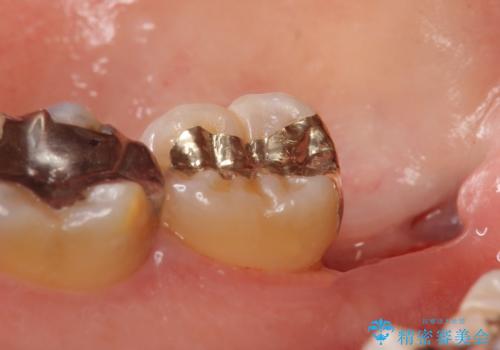

- 右下奥歯がたまにしみるので診て欲しいといらっしゃった方の症例です。

右下7番目の歯の歯茎より深い位置に虫歯があったため、親知らずを抜歯後PGA(ゴールド)インレーによる修復を行いました。

- PGA(ゴールド)インレー…¥60,000費用は治療当時の料金となります